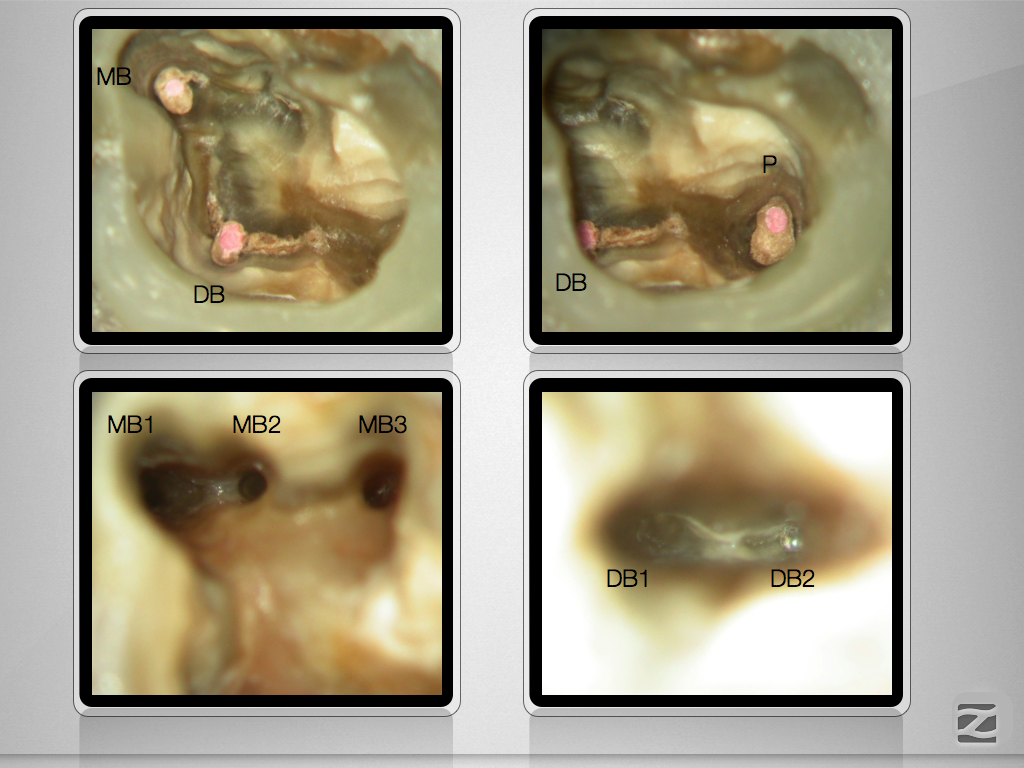

26D.002

Mikado …